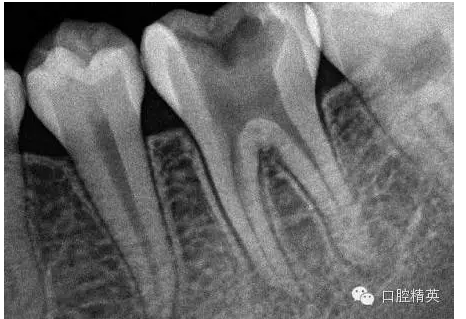

1,術(shù)前X-ray,常規(guī)術(shù)前攝片,

為患者和自己保留一份客觀記錄。。。

3,術(shù)前左下6近中根管斷針X-P,斷針長度約4MM,根尖慢性炎癥影像。。。